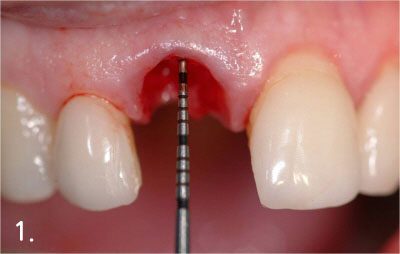

Bone Graft

Gum bone is depressed after extraction

Performing implant placement and bone graft

Implant crown is fabricated after successful bone graft and implant placement

Taking 3D dental CT to evaluate the necessary of bone graft and figure out the amount of bone graft